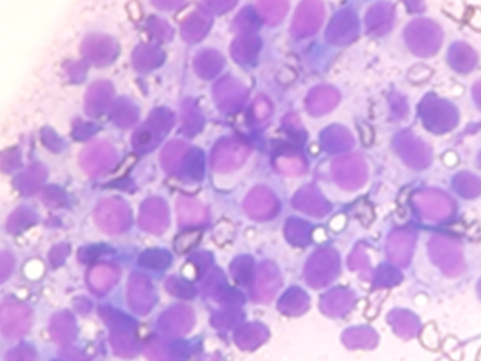

細胞診

細い針で腫瘍の細胞を採取し、染色を行ったあと顕微鏡で細胞の形態を検査します。